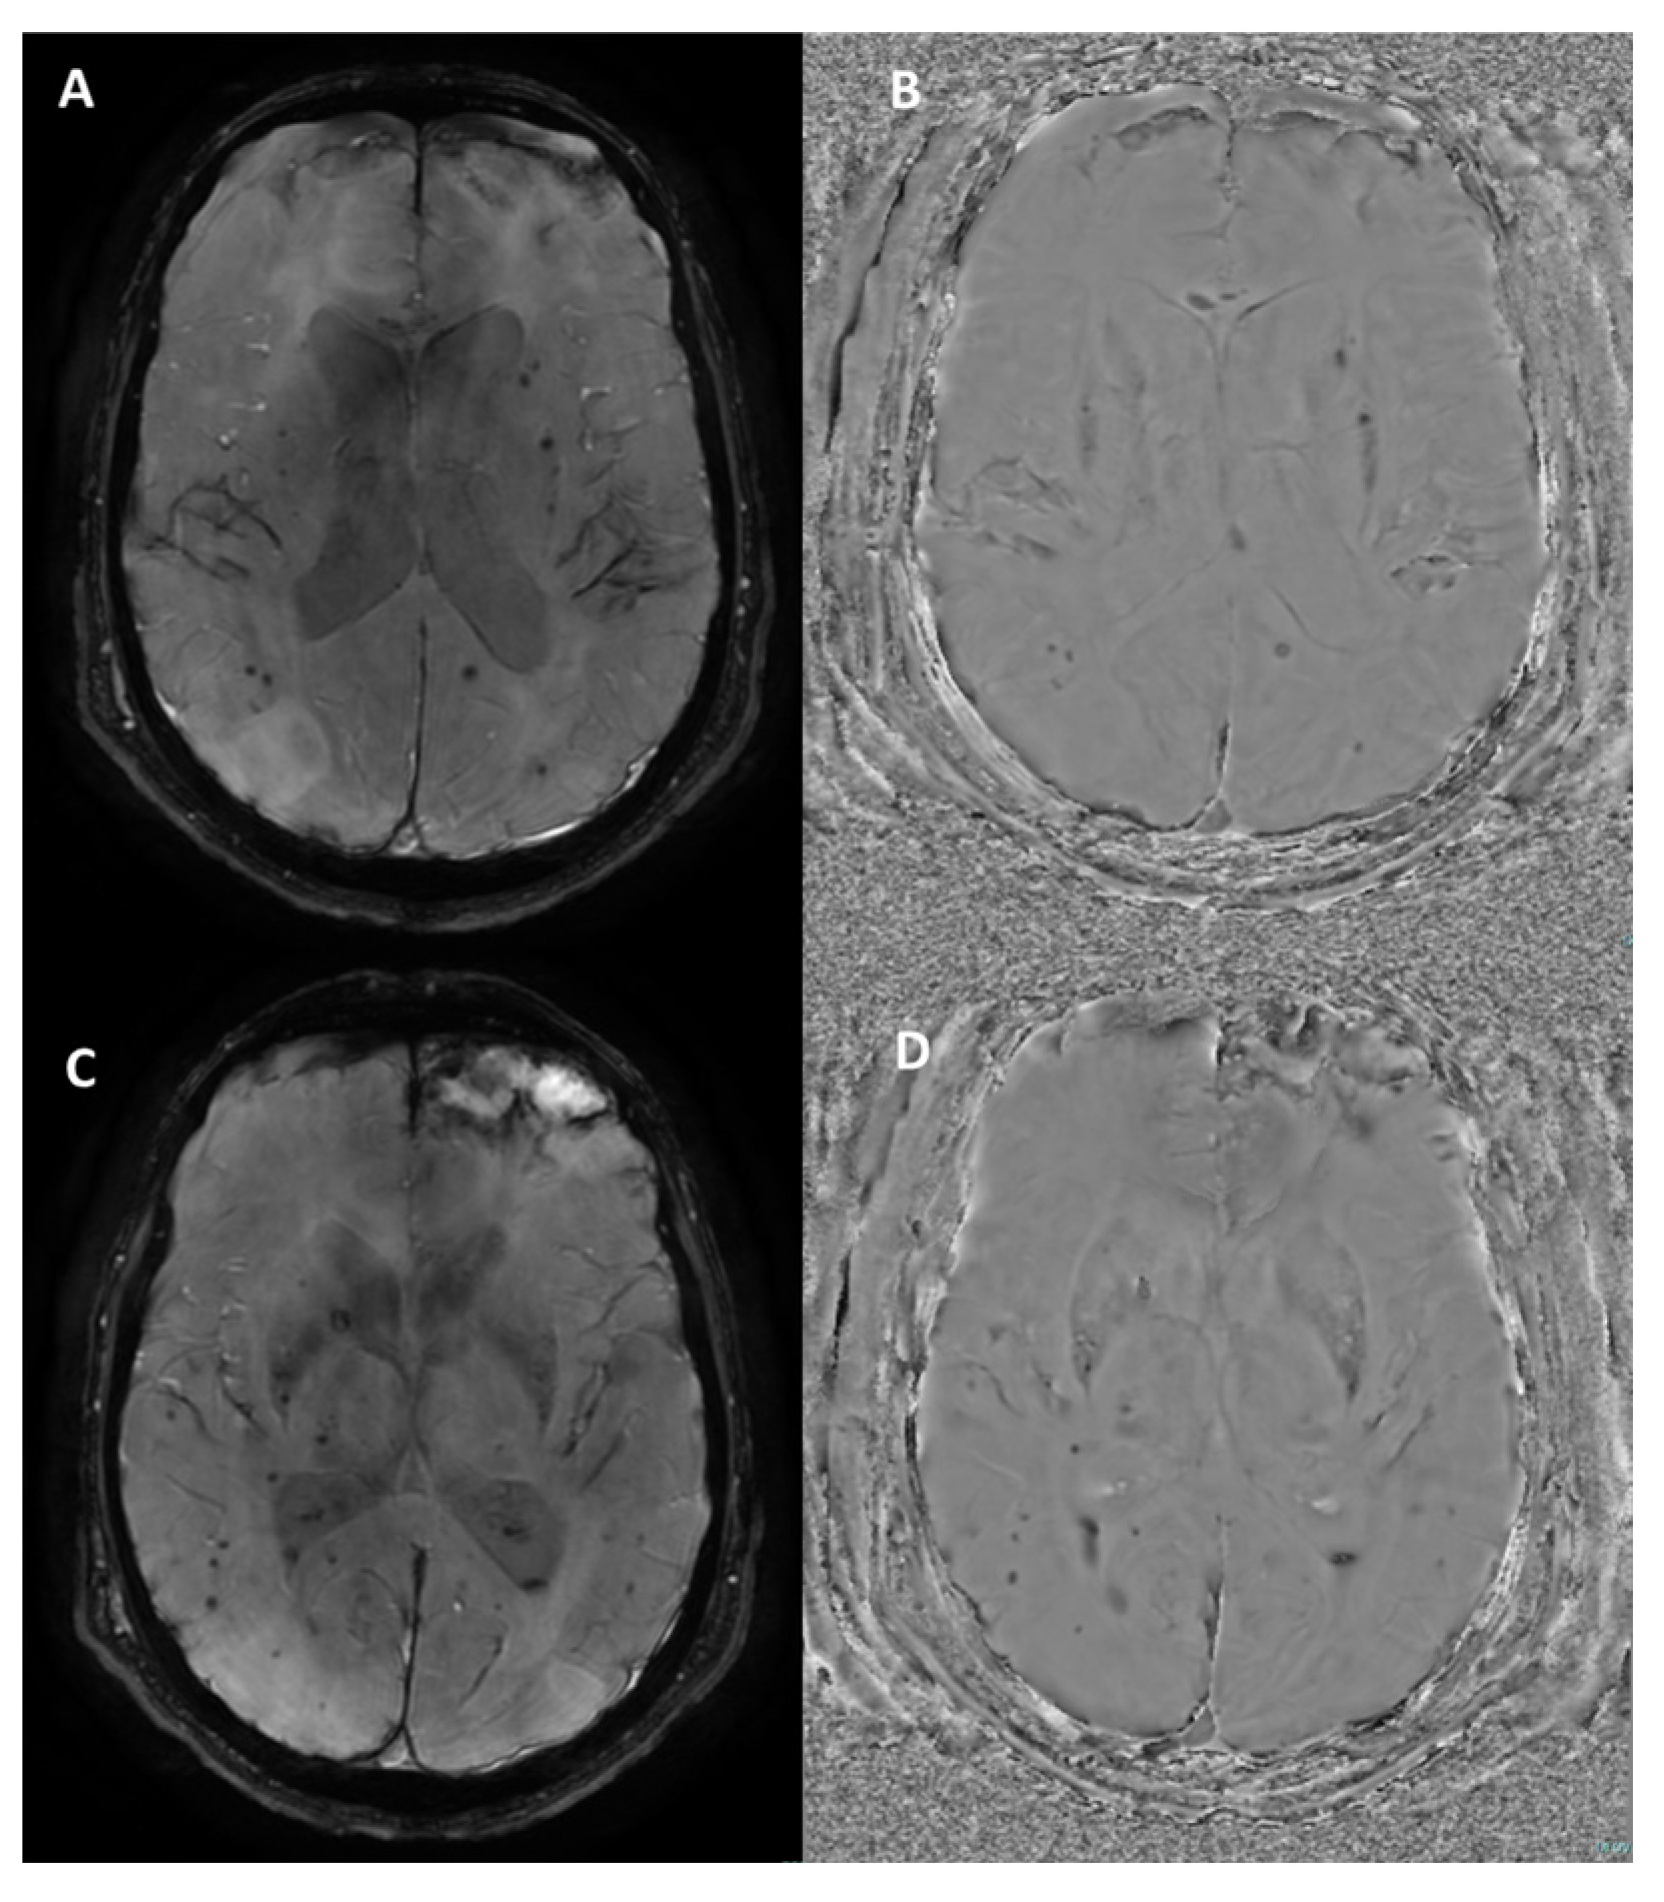

4.2. Multiple Sclerosis

| Multiple sclerosis | Central vein sign | Punctate or linear hypointensity at the center of a hyperintense lesion in at least 2 of 3 orthogonal planes (>2 mm) |

| Paramagnetic rim lesions | Hypointense rim surrounding an internal lesion that is isointense to adjacent normal white matter | |